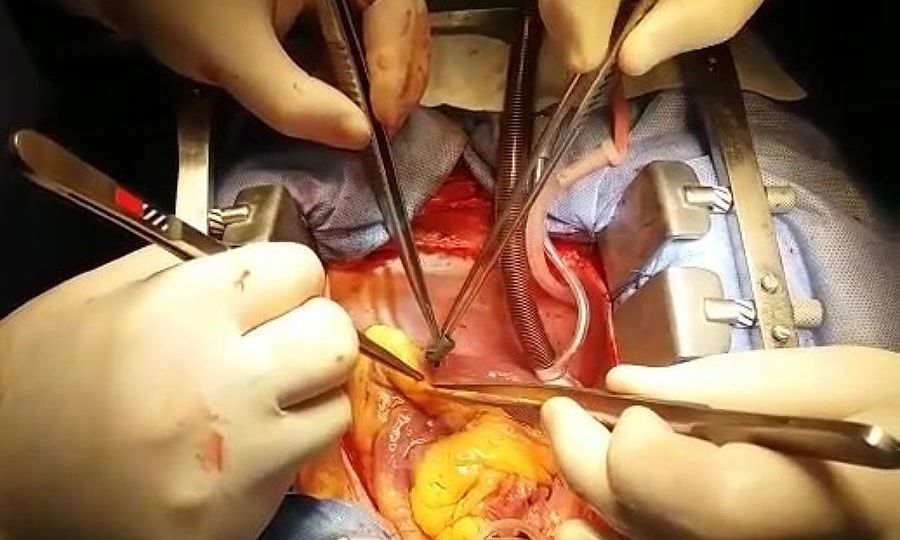

O traumatismo cardíaco relacionado a agressões e acidentes de trânsito é uma das principais causas de morte em todo o…

A endocardite bacteriana aguda é uma doença com alto risco de morbidade e mortalidade, embora desde a década de 1960…

Quando a doença valvar progride ao ponto em que o tratamento médico não proporciona alívio dos sintomas, um médico…